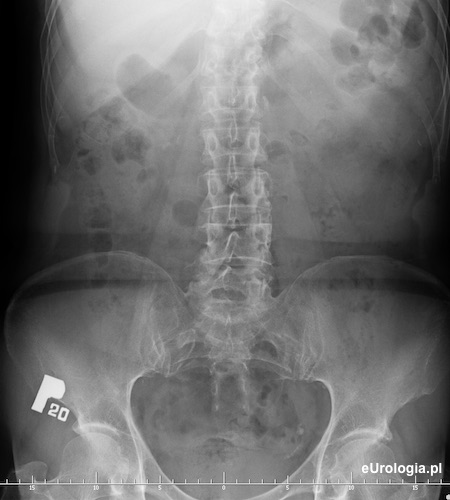

Urografia - wodonercze lewostronne w przebiegu kamicy dolnego odcinka lewego moczowodu

Cień wapienny o wumiarach 9x7 milimetrów w miednicy małej po stronie lewej